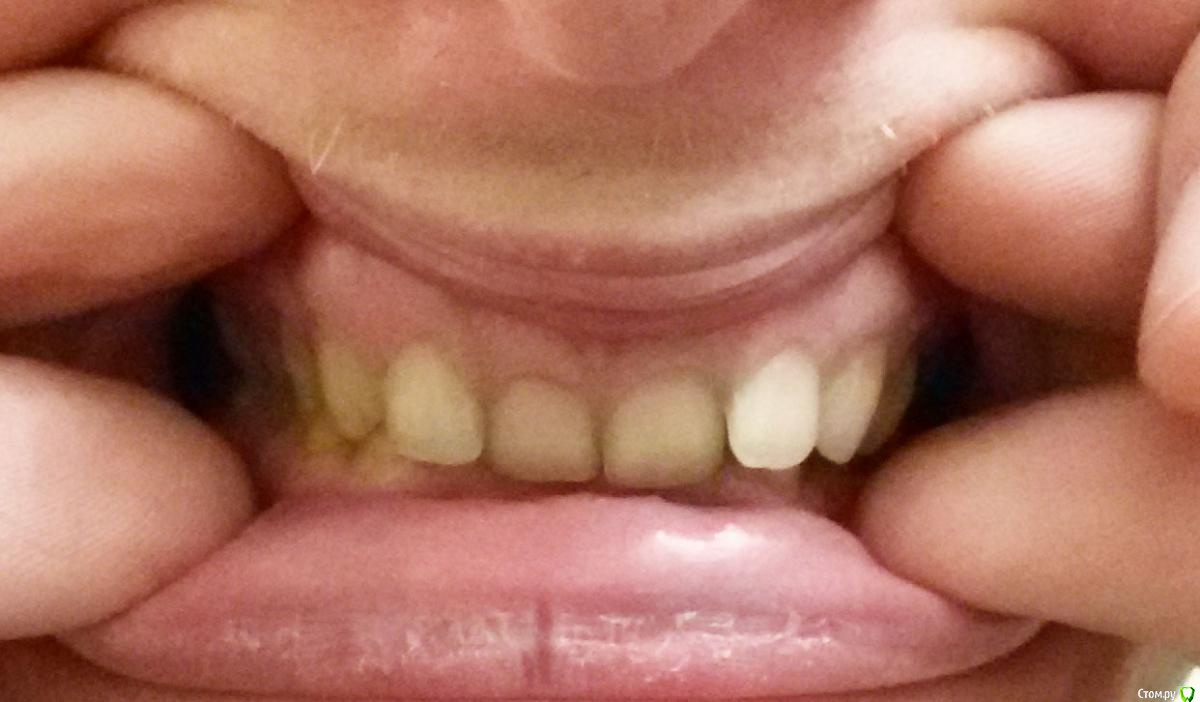

Беспокоит: Возраст 30 лет.  с 15 лет щелчки в суставе, полгода назад появилась периодическая боль - в области сустава, напряжение в жевательных мышцах, в шее  (с шеей вообще давние проблемы - не знаю, что первопричина болей), боли в затылке, голове. Глубокий прикус. Решил прикус исправлять в надежде, что боли уменьшатся.  На снимках видно, что челюсть нижняя заблокирована в заднем положении, мешают верхние резцы, головка сустава смещена

Часть из этого прикрепляю сюда. Ниже - заключение МРТ

Частичное переднее смещение суставного диска ВНЧС справа в положении с закрытым ртом, полная репозиция диска в положении с открытым ртом. Частичное переднее смещение наружного отдела суставного диска ВНЧС слева в положении с закрытым ртом (за счёт внутренней ротации диска), полная репозиция диска в положении с открытым ртом. Остеоартроз ВНЧС справа 1 ст.